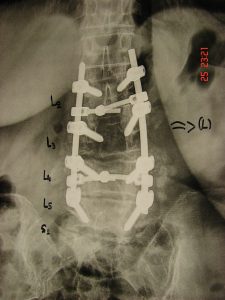

Εικόνα 1 (α,β,γ,δ) Προσθιοπισθία και πλαγία δυναμικές ακτινογραφίες σε κάμψη-έκταση της Ο.Μ.Σ.Σ. Παρατηρείται έκκεντρη καθίζηση στο επίπεδο Ο3-Ο4 και  αστάθεια της περιοχής.

Εικόνα 4 (α,β) 1η Μετεγχειρητική Προσθιοπισθία και πλάγια ακτινογραφία Σπονδυλικής Στήλης σε ορθία στάση. Η σπονδυλοδεσία έγινε για σταθεροποίηση της ασταθούς περιοχής Ο3-Ο4 και εκτείνεται από τον 2ο μέχρι τον 5ο οσφυϊκό σπόνδυλο.

Εικόνα 5 (α,β,γ,δ,ε,ζ) Μετεγχειρητική προσθιοπισθία και πλαγία ακτινογραφία, 4 χρόνια μετά τη σπονδυλοδεσία. Διατηρείται η καλή θέση της Σπονδυλικής Στήλης, όμως η ασθενής αλγεί έντονα στην οσφυοϊερή περιοχή. Οι δυναμικές ακτινογραφίες σε κάμψη-έκταση και κάμψη προς τα αριστερά και δεξιά, δείχνουν αστάθεια στο επίπεδο Ο4-Ο5. Η αστάθεια αποδίδεται στη μειωμένη σταθερότητα των κοχλίων μέσα στο σπονδυλικό σώμα του Ο5 σπονδύλου.